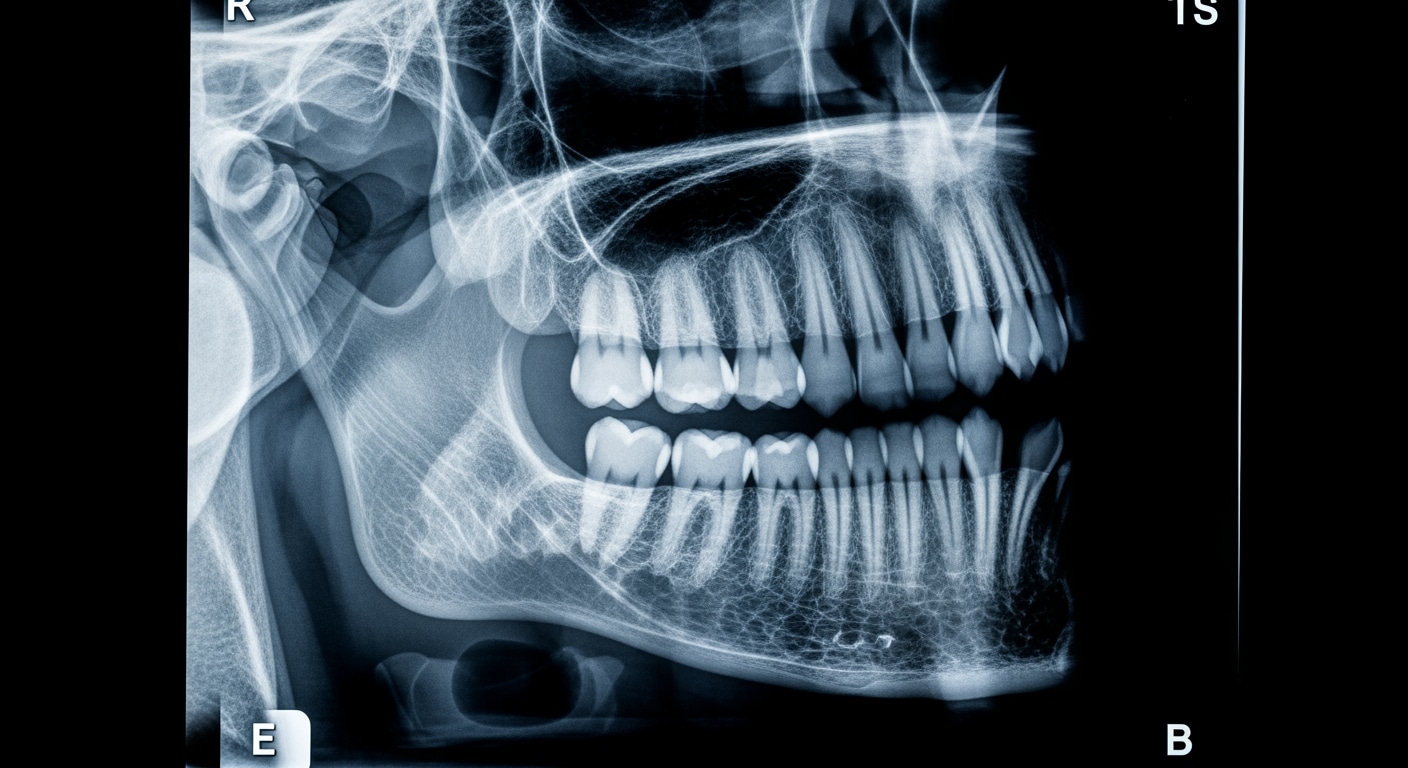

• Head injuries with loss of consciousness or severe impact

Upon arrival at Priority ER for emergency x-ray services, patients bypass traditional triage delays through our zero-wait protocol. Board-certified emergency physicians trained in trauma medicine begin assessment immediately, utilizing digital radiography systems that produce high-resolution images in seconds rather than minutes[9]. This comprehensive approach identifies life-threatening conditions that general urgent care facilities would miss, such as pneumothorax requiring chest tube, displaced fractures needing immediate reduction, or internal bleeding requiring emergency surgery.

Priority ER's diagnostic capabilities for emergency x-ray services exceed Joint Commission standards for emergency departments[14], featuring digital radiography systems typically found only in major trauma centers. Our x-ray system produces images with 99% diagnostic accuracy compared to conventional film standards, enabling detection of subtle fractures, pneumothorax as small as 5%, and foreign bodies requiring surgical removal[15]. The integration of picture archiving and communication systems (PACS) allows instant image transmission to consulting orthopedic surgeons when complex fractures require specialized surgical planning.

Advanced imaging diagnostics through our comprehensive capabilities include not just standard x-ray views but also CT scanning, ultrasound, and specialized radiographic series for complex trauma evaluation. For patients with multi-system injuries, our imaging department performs trauma series protocols, dedicated spine imaging, and advanced reconstructions automatically, crucial for identifying life-threatening injuries that standard urgent care x-rays cannot fully assess. This technology gap explains why the American College of Emergency Physicians recommends freestanding ERs over urgent care for all significant trauma requiring immediate comprehensive imaging.

Can Priority ER perform x-rays for children and infants?

Absolutely. Our pediatric-trained emergency physicians and radiology technologists perform x-ray imaging on children of all ages using age-appropriate techniques and equipment. Pediatric x-ray imaging requires specialized training in radiation dose optimization, immobilization techniques, and pediatric fracture pattern recognition, which our staff maintains through continuous education. Our pediatric emergency services ensure child-friendly approaches with minimal anxiety, parent presence during imaging, and maximum safety.